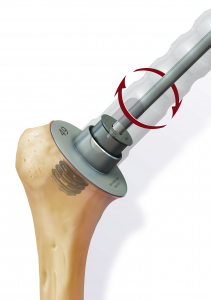

Anschließend wird der zerstörte Oberarmkopf entlang der Schnittlinie mit Hilfe einer Resektionslehre entfernt (Abb. 39). Mit einer Bohrschablone wird das Einbringen der Hohlschraube vorbereitet (Abb. 40) und die definitive Prothesengröße bestimmt. Nun kann bei freier Sicht auf die Gelenkspfanne selbige ausgetauscht werden, sofern dies aufgrund fortgeschrittener Erkrankung nötig ist (Abb. 41).

Daraufhin wird der Kalottenträger mittels der selbstschneidenden Hohlschraube im Oberarmschaft befestigt. Nun wird der endgültige Prothesenkopf angebracht (Abb. 49).